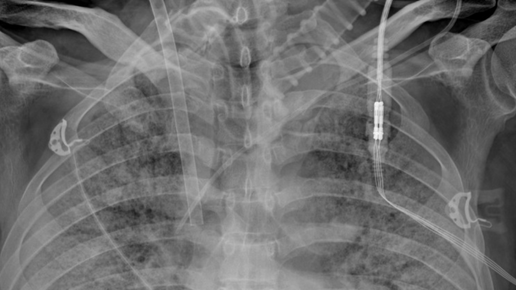

Этот мужчина 43 лет за неделю до болезни вернулся с отдыха в одной из южных стран. Почувствовал слабость, одышку, Т тела повышалась до 39-40 С. Лечился самостоятельно, в/м инъекциями цефалоспоринов с положительным эффектом - снизилась температура тела. Однако, чуть позже вновь появилась лихорадка, сухой кашель и одышка - госпитализирован по скорой помощи в инфекционный стационар, при поступлении Sat02 - 88%, сразу налажена респираторная поддержка (10 л/мин), госпитализация в отделение реанимации и интенсивной терапии...